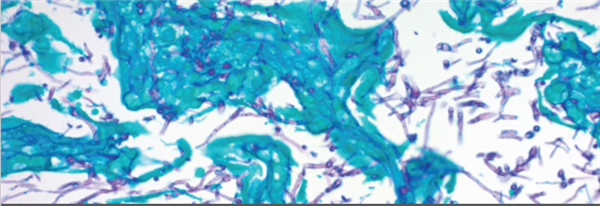

3.Cat#KAA-1 GMS Stain Kit

组份:肖酸银溶液,甲安硼砂溶液,氯化金溶液,浅绿色溶液,龙胆紫溶液,碘溶液,革兰氏脱色剂,亚硫酸氢纳溶液,氧化液,硫代硫酸纳5%,红色复染,酒石酸溶液

目的:改良的Gomori甲基六胺-肖酸银染色剂(GMS染色试剂盒)旨在用于真菌,基底膜和某些机会性生物(如卡氏肺孢子虫)的组织学可视化。 此外,该程序还将显示放线菌和相关物种,诺卡氏小行星诺卡氏菌和某些包囊细菌。 铬酸和危害较小的替代氧化剂均可使用。

结果图: